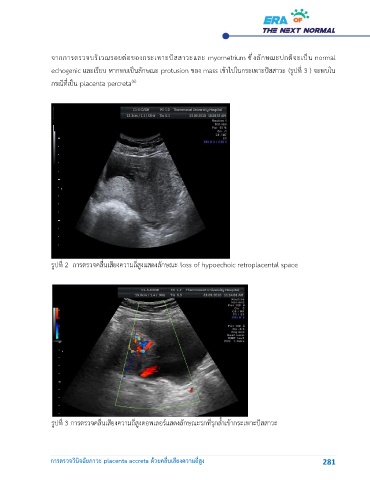

จากการตรวจบริเวณรอยต่อของกระเพาะปัสสาวะและ myometrium ซึ่งลักษณะปกติจะเป็น normal

echogenic และเรียบ หากพบเป็นลักษณะ protusion ของ mass เข้าไปในกระเพาะปัสสาวะ (รูปที่ 3 ) จะพบใน

กรณีที่เป็น placenta percreta

รูปท 2 การตรวจคลื่นเสียงความถี่สูงแสดงลักษณะ loss of hypoechoic retroplacental space

รูปท 3 การตรวจคลื่นเสียงความถี่สูงดอพเลอร์แสดงลักษณะรกที่รุกล้ำเข้ากระเพาะปัสสาวะ